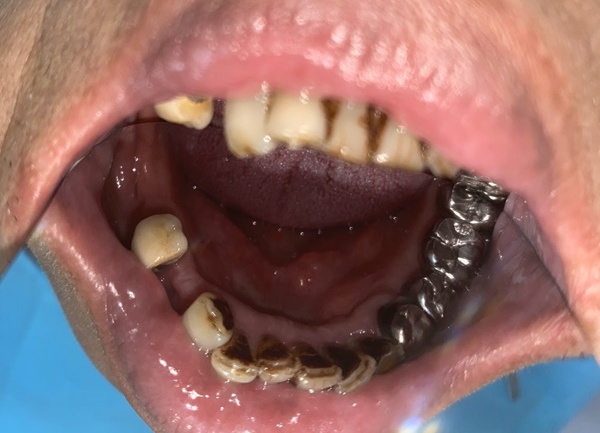

我平時上班忙,兩三個月回家一次,才發現媽媽缺牙狀況越來越嚴重,活動假牙也因為她覺得口腔會有異物感和時常磨破皮不太喜歡配戴。身為從小她寵愛到大的獨生女,最後決定帶媽媽去做植牙。

缺牙長期不補首先會面臨牙齒倒塌的問題,會從鄰牙開始往缺牙處傾倒,移動牙齒位置,再來會有牙齦、齒槽骨萎縮的現象

手術前先到診所做斷層掃描和諮詢,媽媽因為長期缺牙,骨質與骨量不佳,所以要先補骨粉。雲康牙醫可以線上預約,回覆的速度也很快,約診前一天時小護士都會非常貼心的傳送訊息提醒預約時間,揪甘心ㄟ!